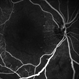

- occlusive vasculitis, optic disc pallor, macular ischemia

- Fundus photograph of left eye of a 23-year-old gentleman with Behcet's Disease shows occlusive retinal vasculitis with optic disc pallor and macular ischemia. This eye has no light perception; other eye has similar fundus appearance.